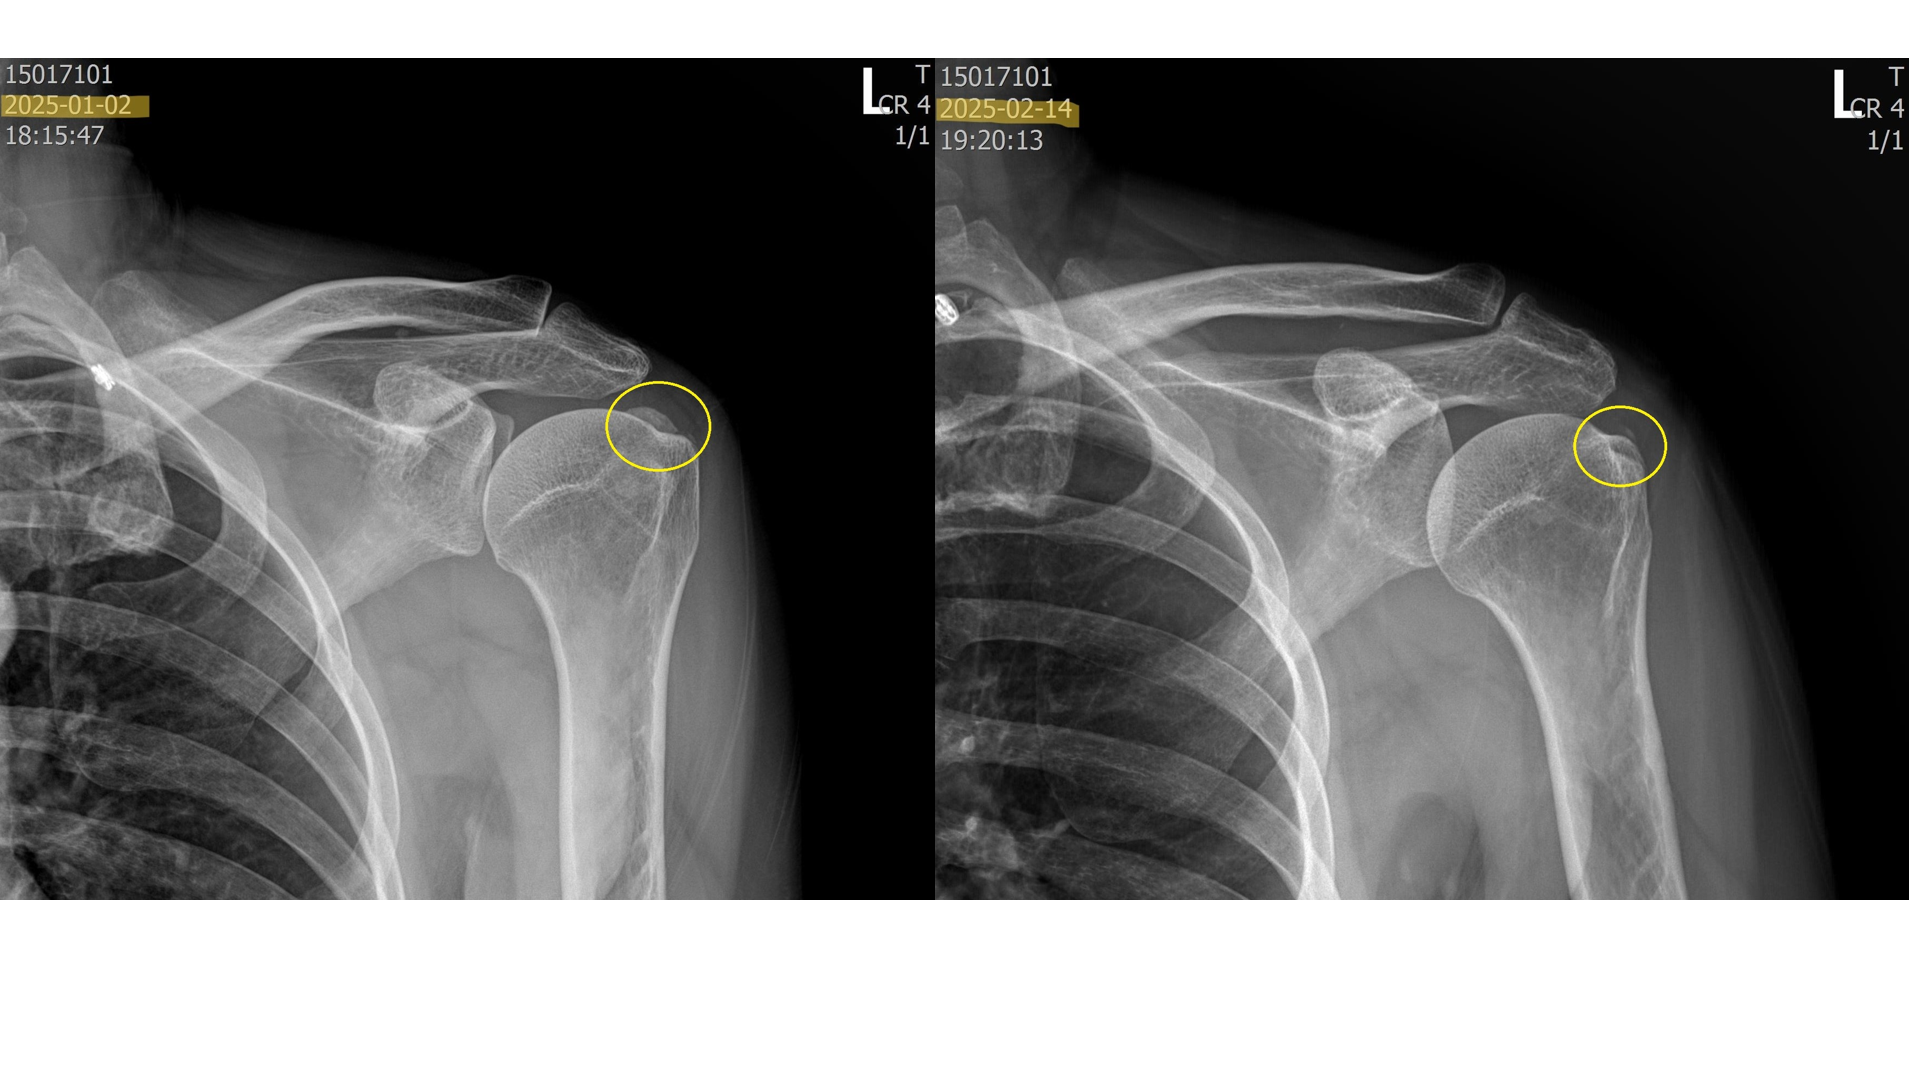

비포 VS 애프터 (석회흡입술과 체외충격파 치료 5회)

위의 사진은 실제로 내원하여 치료받은 환자들의 x-ray 입니다. 이 환자분들은 약 5회에 걸쳐 섭회흡입술 + 체외충격파시술을 받은 분들입니다. 보시다시피 드라마틱하게 석회가 제거된걸 볼 수 있습니다.